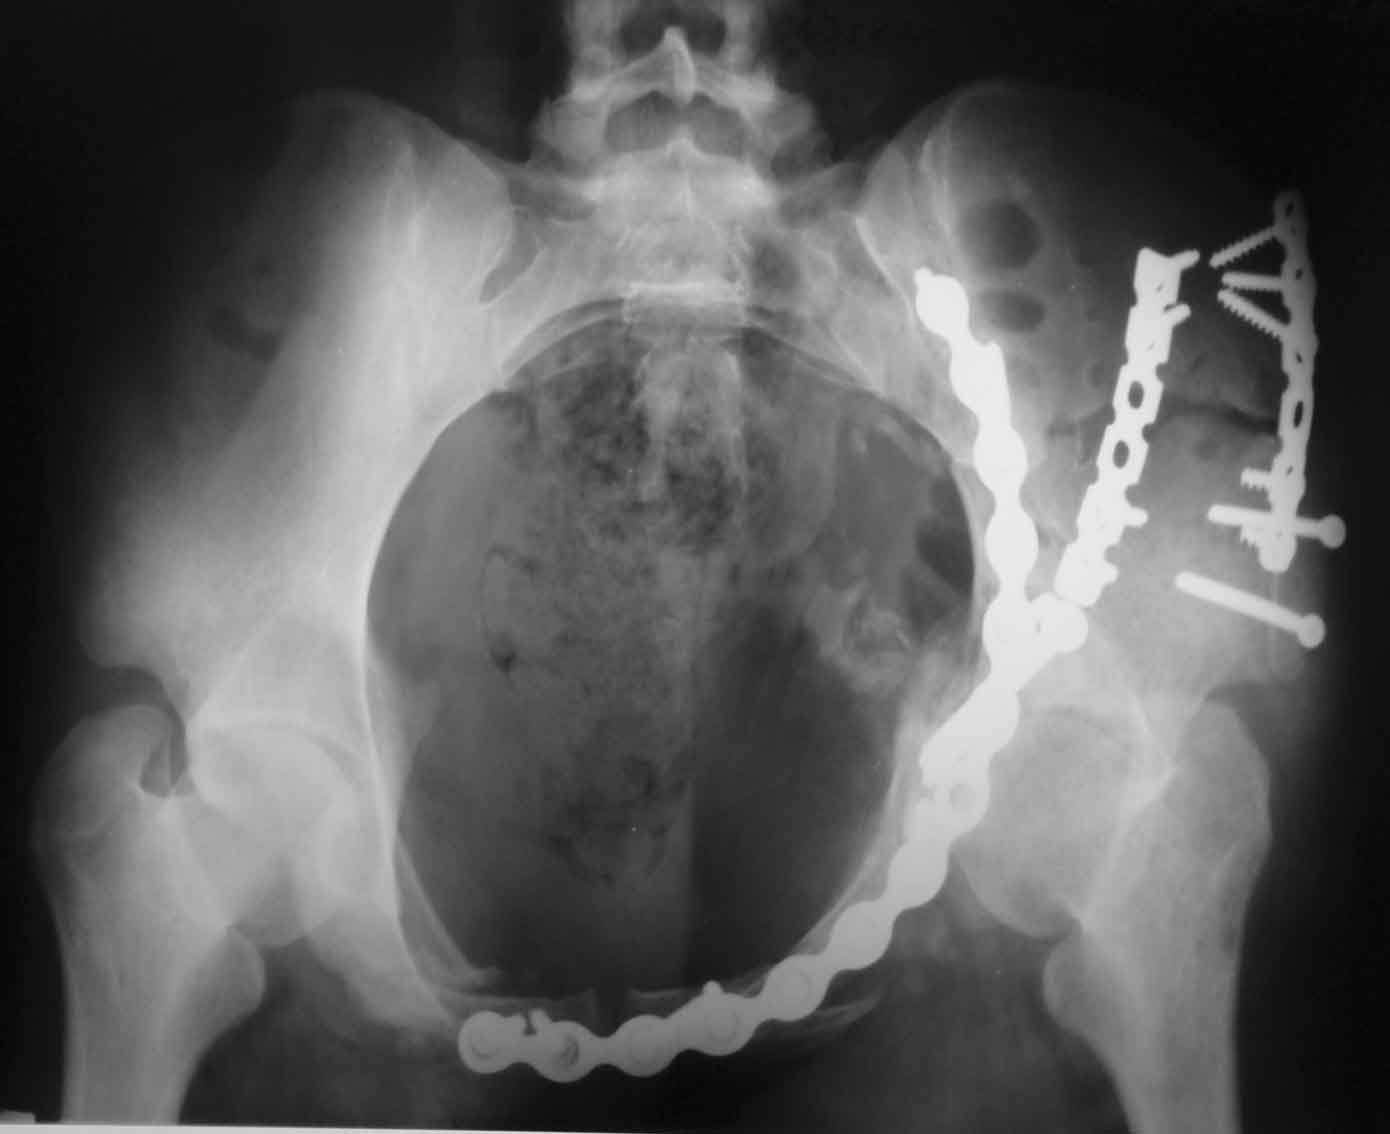

Рентгенограммы после операции

подвздошная

A>РО - картина не очень, есть видимость винтов во впадине

По всей видимости, вы имеете в виду канюлированный винт, который проецируется на вертлужной впадине. Та вот, он проведен не через лонную, а седалищную кость. Вертлужная впадина абсолютно интактна. Это хорошо видно на проекции inlet.